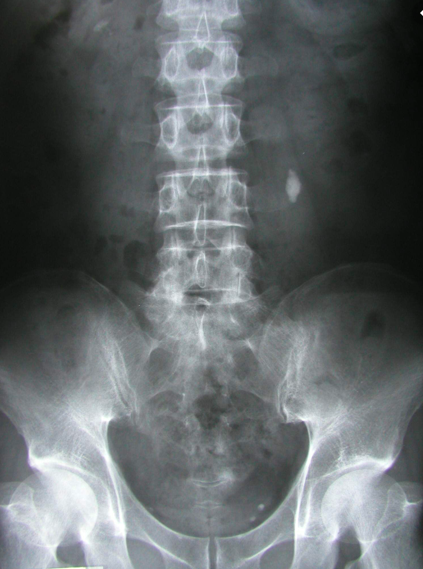

What is this abdominal x-ray showing?